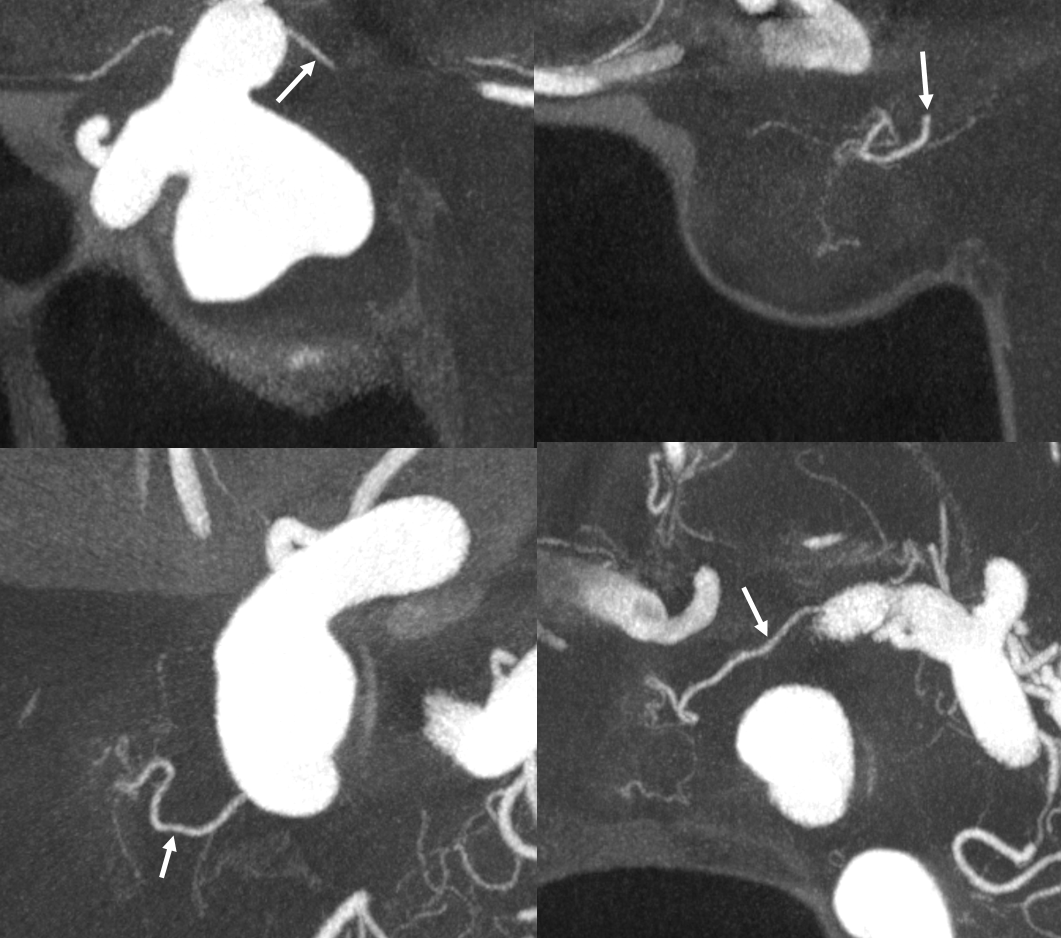

Optic Nerve Supply

What supplies the bulk of optic nerve? Central Retinal artery is for the distal portion of nerve and retina. What about the rest — intracranial, intracanalicular, proximal intraconal segments? The answer is not clear (let me know if you do), but i believe the bulk of it comes from the superior hypophyseals. It is probably in balance with the recurrent branch of the central retinal artery. Below is an example of an especially prominent proximal-most superior hypophyseal (arrows) supplying the pituitary stalks and optic nerve in the canalicular and intracranial locations. Note how well one can see the branch in coronal view (bottom left image). In this case there are two large superior hypophyseals — the more distal one (dashed arrows) supplies predominantly the pituitary stalk. The inferior hypophyseal artery is marked by arrowhead. Lower right image is coronal.

Movie is the best way

Here too superior hypophyseal (arrow) supply of the intracranial optic nerve (oval) and possibly chiasm is shown definitively (lower right image is coronal)

No annotations

Best seen in this movie (pause to scroll)